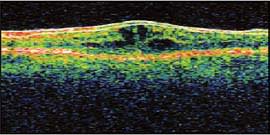

A 74 year-old male with a 15 year history of non-insulin-dependent diabetes presented for a routine cataract procedure. There were no intraoperative complications and he did very well post-procedure. At the time of his 1-month postoperative exam, his vision had declined to 20/70. Optical coherence tomography (OCT) revealed classic cystoid macular edema (CME).

Figure 1. Typical cystic spaces confirming the diagnosis of CME (abnormal).